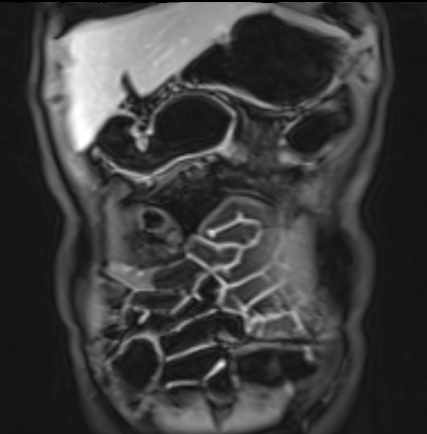

Bệnh nhân nữ 48 tuổi, đang điều trị bằng thuốc kháng TNF, được chỉ định nội soi đại tràng.

Phát hiện hẹp lòng ruột ở đại tràng sigma, không thể vượt qua được khi nội soi.

MR-enterography được thực hiện để đánh giá mức độ lan rộng của chỗ hẹp.

Ruột non bình thường, nhưng ghi nhận các đoạn hẹp ở đại tràng xuống và đại tràng ngang.

Cả hai đoạn hẹp đều có thành ruột dày đến 8 mm và ngấm thuốc rõ rệt theo kiểu niêm mạc ở đại tràng xuống và kiểu phân lớp ở đại tràng ngang.

Giãn ruột trước chỗ hẹp được ghi nhận ở cả hai đoạn.

Do các chỗ hẹp này không hiện diện khi nội soi đại tràng trước khi điều trị kháng TNF, nhiều khả năng chúng đã hình thành trong quá trình điều trị.

Do đó, quyết định phẫu thuật cắt đại tràng gần toàn bộ với miệng nối hồi-sigma đã được đưa ra.